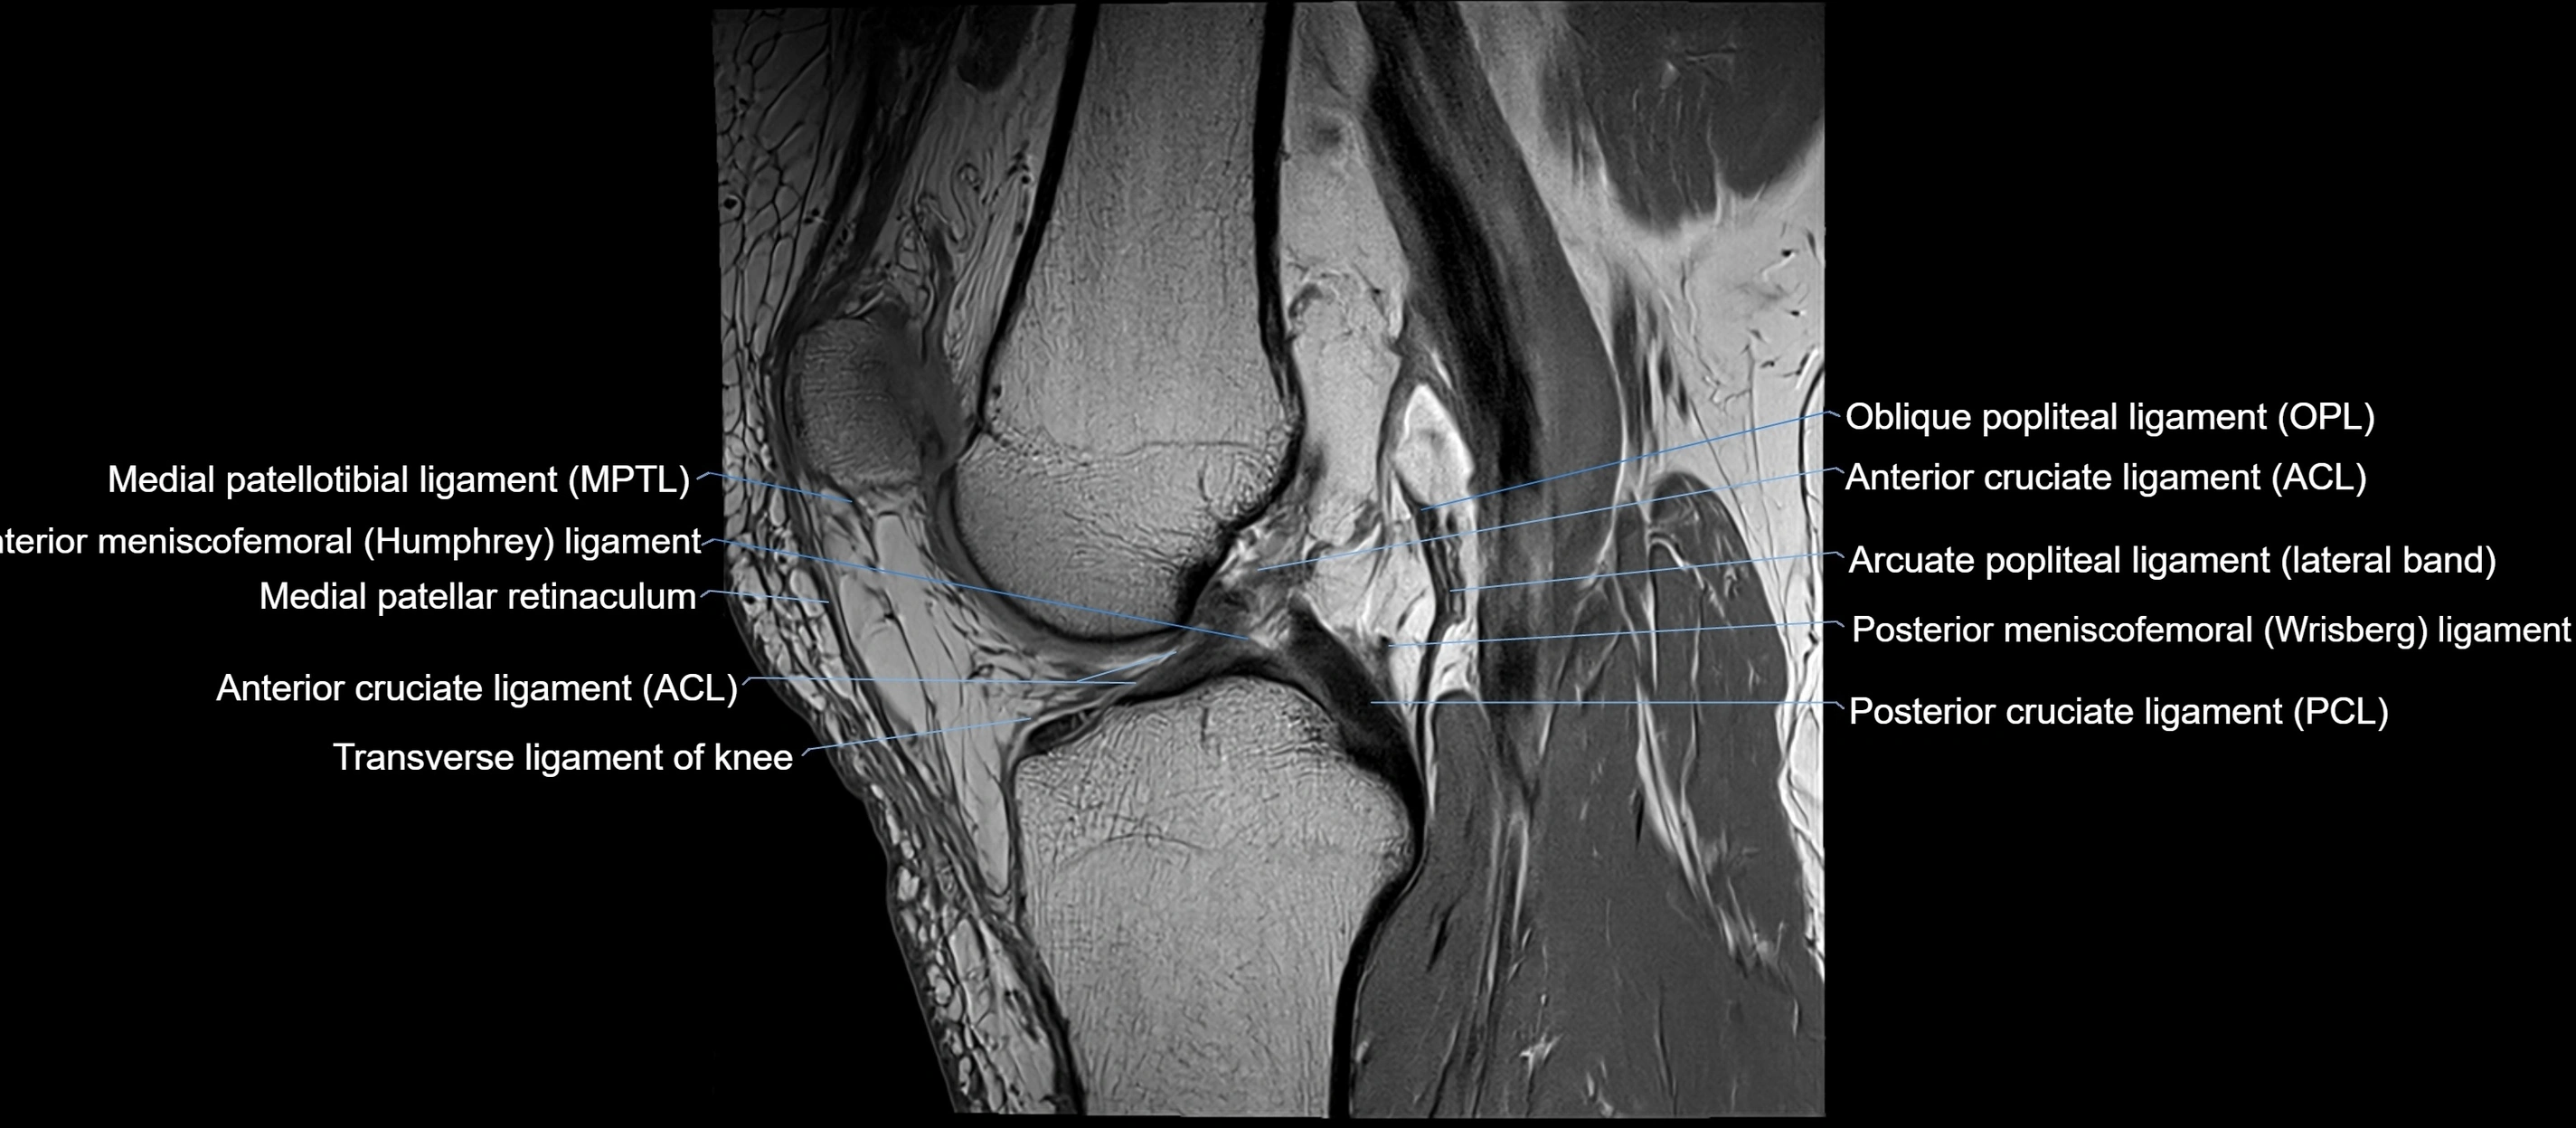

MRI Appearance

T1-weighted images:

• Normal ACL appears as a low-signal band-like structure crossing the intercondylar notch

• Surrounded by intermediate signal synovial fluid and fat planes

T2-weighted images:

• Normal ACL remains low signal

• Partial or complete tears appear as discontinuity, increased signal, or fiber laxity

MRI images

image